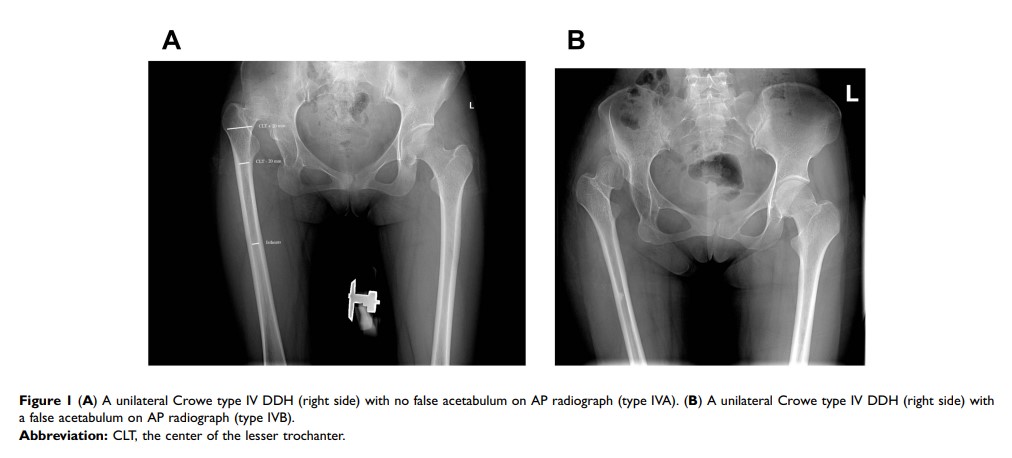

在单侧 Crowe IV 型髋关节发育不良脱位中,假髋臼对股骨近端髓管的影响